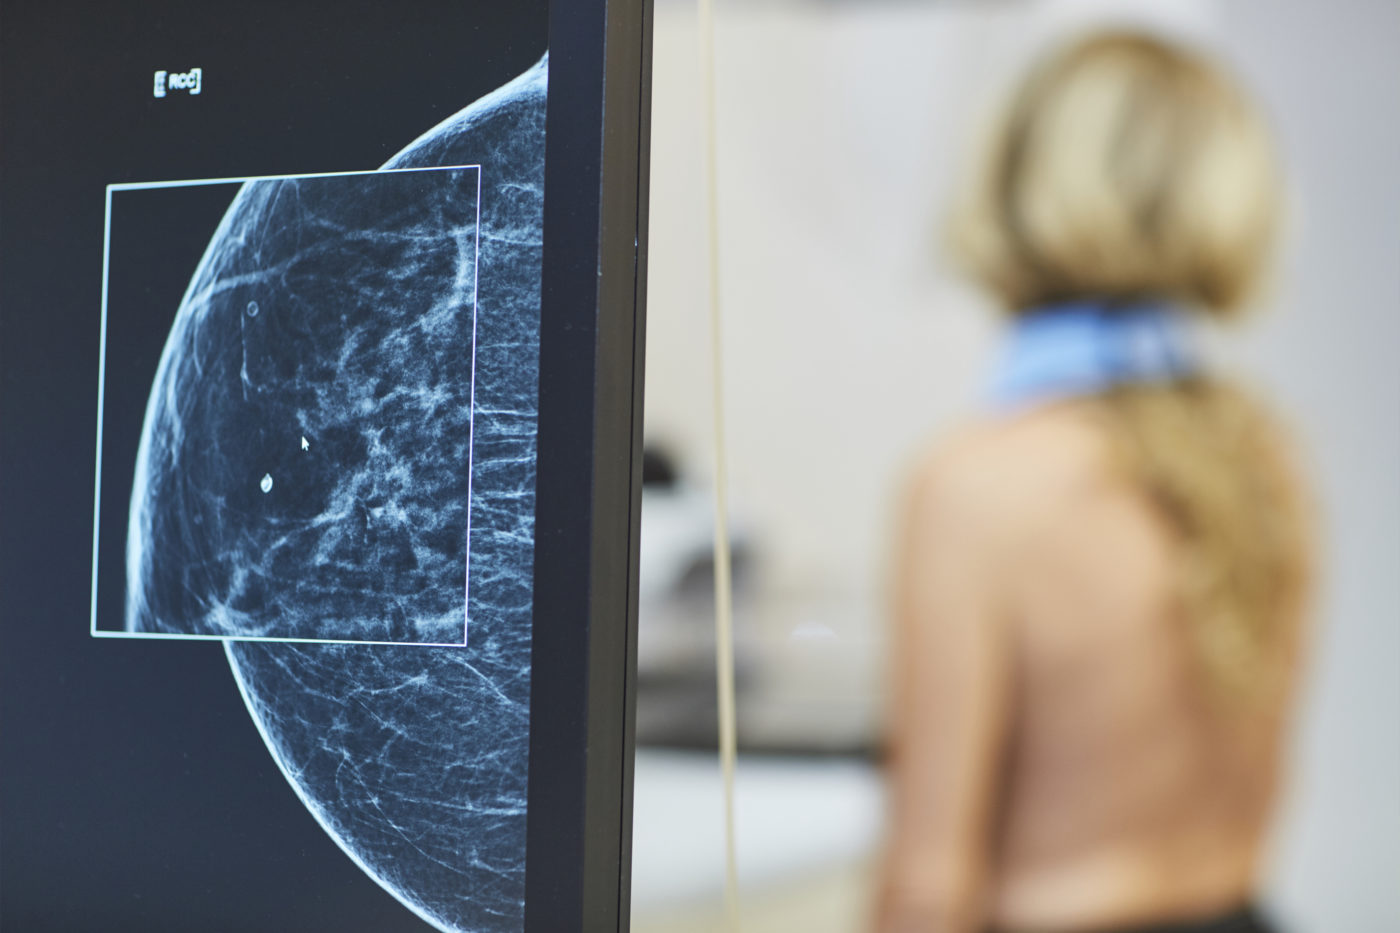

„Mikrokalcifikáty môžu byť v úplne skorom štádiu viditeľné len na mamografii, často ide o zmeny veľké len niekoľko milimetrov. Práve preto je mamografické vyšetrenie také dôležité a nenahraditeľné. Väčšie zmeny môžu byť neskôr viditeľné aj na ultrazvuku,“

vysvetľuje MUDr. Alexandra Bieliková, lekárka rádiológie AGEL Mammacentra sv. Agáty.

Lekári pri hodnotení mikrokalcifikátov sledujú viacero znakov, napríklad ich veľkosť, tvar, hustotu, rozloženie v prsníku či to, ako sa menia v čase. Práve tieto informácie pomáhajú určiť, či ide o bežný a neškodný nález, alebo o zmenu, ktorú treba podrobnejšie vyšetriť.